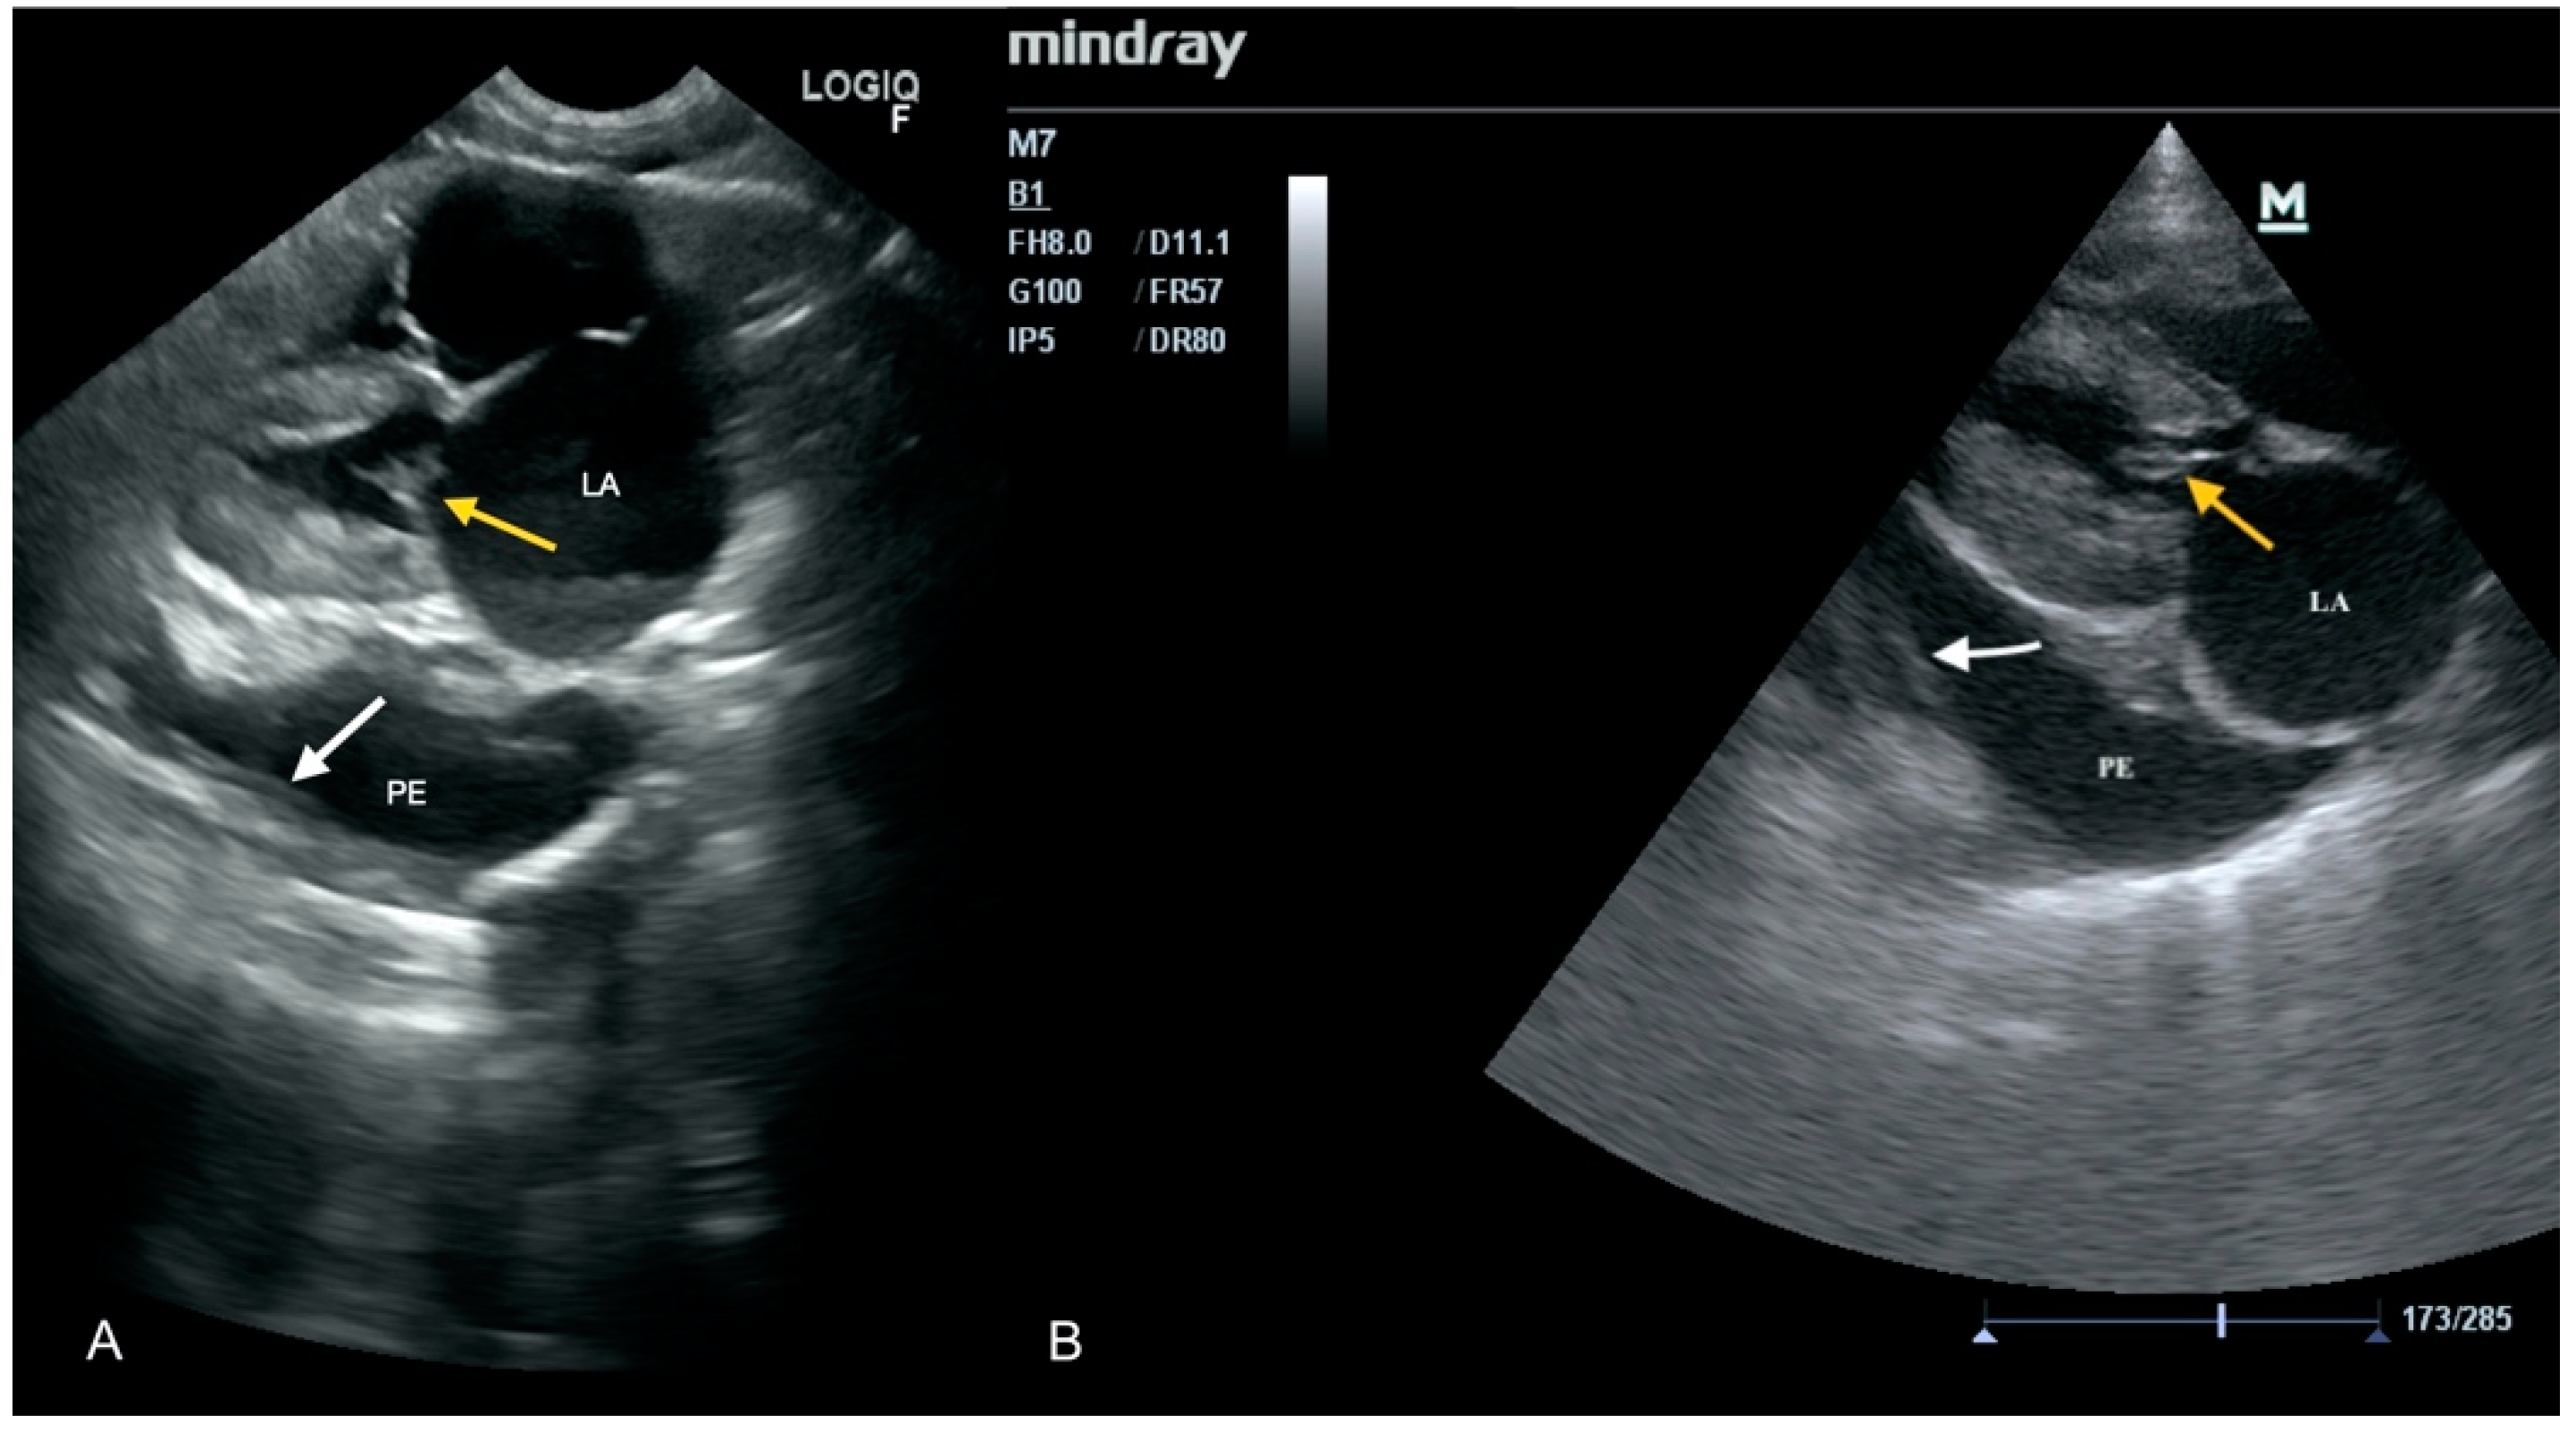

3.1. Case No. 1

3.2. Case No. 2